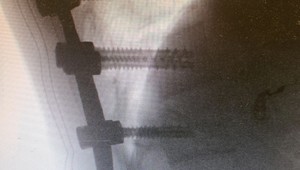

Neurochirurg varuje: Rodičia, nedovoľte deťom skákať hlavičky do záhradných bazénov! Zdravie a rodina

Traumatológovia: Úrazy detí na trampolínach sa množia. Toto je 7 vecí, ktoré pri skákaní nedovoľte! Zdravie a rodina